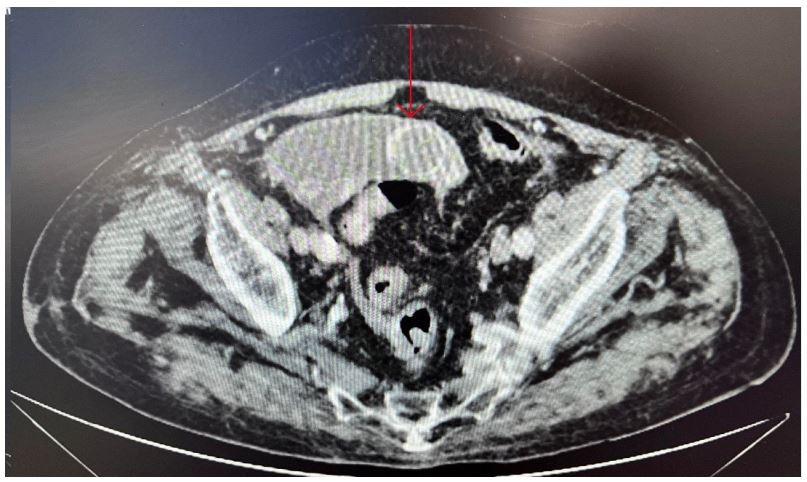

In light of these observations, an abdominal CT scan was requisitioned. The ensuing abdominal CT scan unveiled the presence of a nodular structure measuring approximately 30 mm within the lumen of the ileal loop. This condition was accompanied by dilation of the upstream loop, marked by ectasia encompassing the stomach. Additionally, multiple discrete areas of calculi were discerned within the gallbladder, though no indications of acute cholecystitis were noted (Figure 1).

Figure 1: Axial section of the Abdominal CT scan - It can be seen as identified by the arrow a nodular structure within the lumen of the ileal loop.